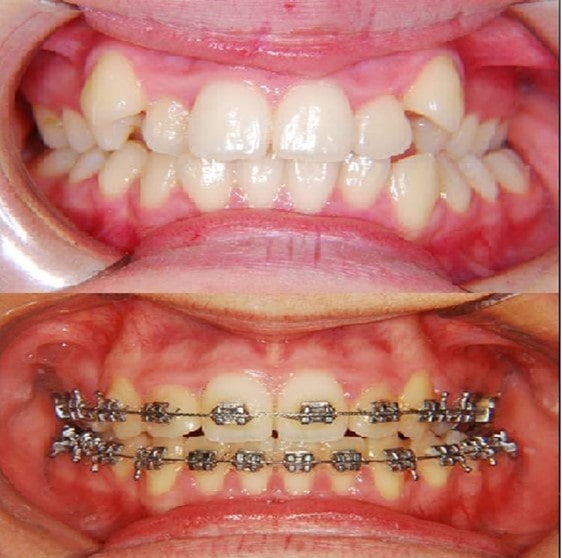

رایج ترین روش برای درمان دندان نیش بیرون زده استفاده از بریس و سایر ابزار ارتودنسی است. ارتودنسی شامل استفاده از بریس برای اصلاح موقعیت دندانها است. درمان دقیق شما به مشکل دندان شما بستگی دارد.

رایج ترین روش برای درمان دندان نیش بیرون زده استفاده از بریس و سایر ابزار ارتودنسی است. فشار بریسها به تغییر موقعیت دندانها و مرتب شدن آنها کمک میکند.

به تدریج فشار وارد شده به دندانها به فرستادن دندان نیش بیرون زده به جای خود کمک میکند و دندانهای بیمار مرتب میشوند. در نتیجه بیمار میتواند یک لبخند زیبا داشته باشد.

ارتودنسی برای دندانهای نیش نهفته

بریسها میتوانند دندان نیش نهفته را به موقعیت صحیح خود بکشند. دندان در حالت عمودی و در موقعیت صحیح میتواند به عملکرد گاز زدن و جویدن کمک کند.